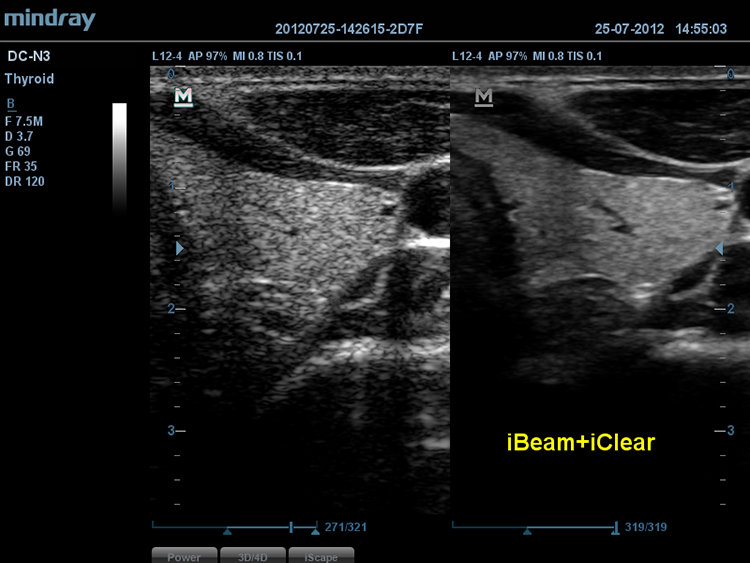

iBeamTM

–Я–Њ–Ј–≤–Њ–ї—П–µ—В –Є—Б–њ–Њ–ї—М–Ј–Њ–≤–∞—В—М –љ–µ—Б–Ї–Њ–ї—М–Ї–Њ —Г–≥–ї–Њ–≤ —Б–Ї–∞–љ–Є—А–Њ–≤–∞–љ–Є—П –і–ї—П —Д–Њ—А–Љ–Є—А–Њ–≤–∞–љ–Є—П –µ–і–Є–љ–Њ–≥–Њ –Є–Ј–Њ–±—А–∞–ґ–µ–љ–Є—П, —З—В–Њ –њ—А–Є–≤–Њ–і–Є—В –Ї —Г–≤–µ–ї–Є—З–µ–љ–Є—О –Ї–Њ–љ—В—А–∞—Б—В–љ–Њ–≥–Њ —А–∞–Ј—А–µ—И–µ–љ–Є—П –Є —Г–ї—Г—З—И–µ–љ–Є—О –≤–Є–Ј—Г–∞–ї–Є–Ј–∞—Ж–Є–Є.

iClearTM

–Я–Њ–Ј–≤–Њ–ї—П–µ—В —Г–ї—Г—З—И–Є—В—М –Ї–∞—З–µ—Б—В–≤–Њ –Є–Ј–Њ–±—А–∞–ґ–µ–љ–Є—П, –Њ—Б–љ–Њ–≤—Л–≤–∞—П—Б—М –љ–∞ –∞–≤—В–Њ–Љ–∞—В–Є—З–µ—Б–Ї–Њ–Љ —А–∞—Б–њ–Њ–Ј–љ–∞–≤–∞–љ–Є–Є —Б—В—А—Г–Ї—В—Г—А.

- –С–Њ–ї–µ–µ —З–µ—В–Ї–Є–µ –Ї—А–∞—П –Є –Ї–Њ–љ—В—Г—А—Л

- –Я–ї–∞–≤–љ–Њ–µ –Є –Њ–і–љ–Њ—А–Њ–і–љ–Њ–µ –Њ—В–Њ–±—А–∞–ґ–µ–љ–Є–µ —В–Ї–∞–љ–µ–є

- –°–љ–Є–ґ–µ–љ–Є–µ –Ј–µ—А–љ–Є—Б—В–Њ—Б—В–Є –≤ ?–Њ–±–ї–∞—Б—В—П—Е –±–µ–Ј —Н—Е–Њ—Б–Є–≥–љ–∞–ї–∞?